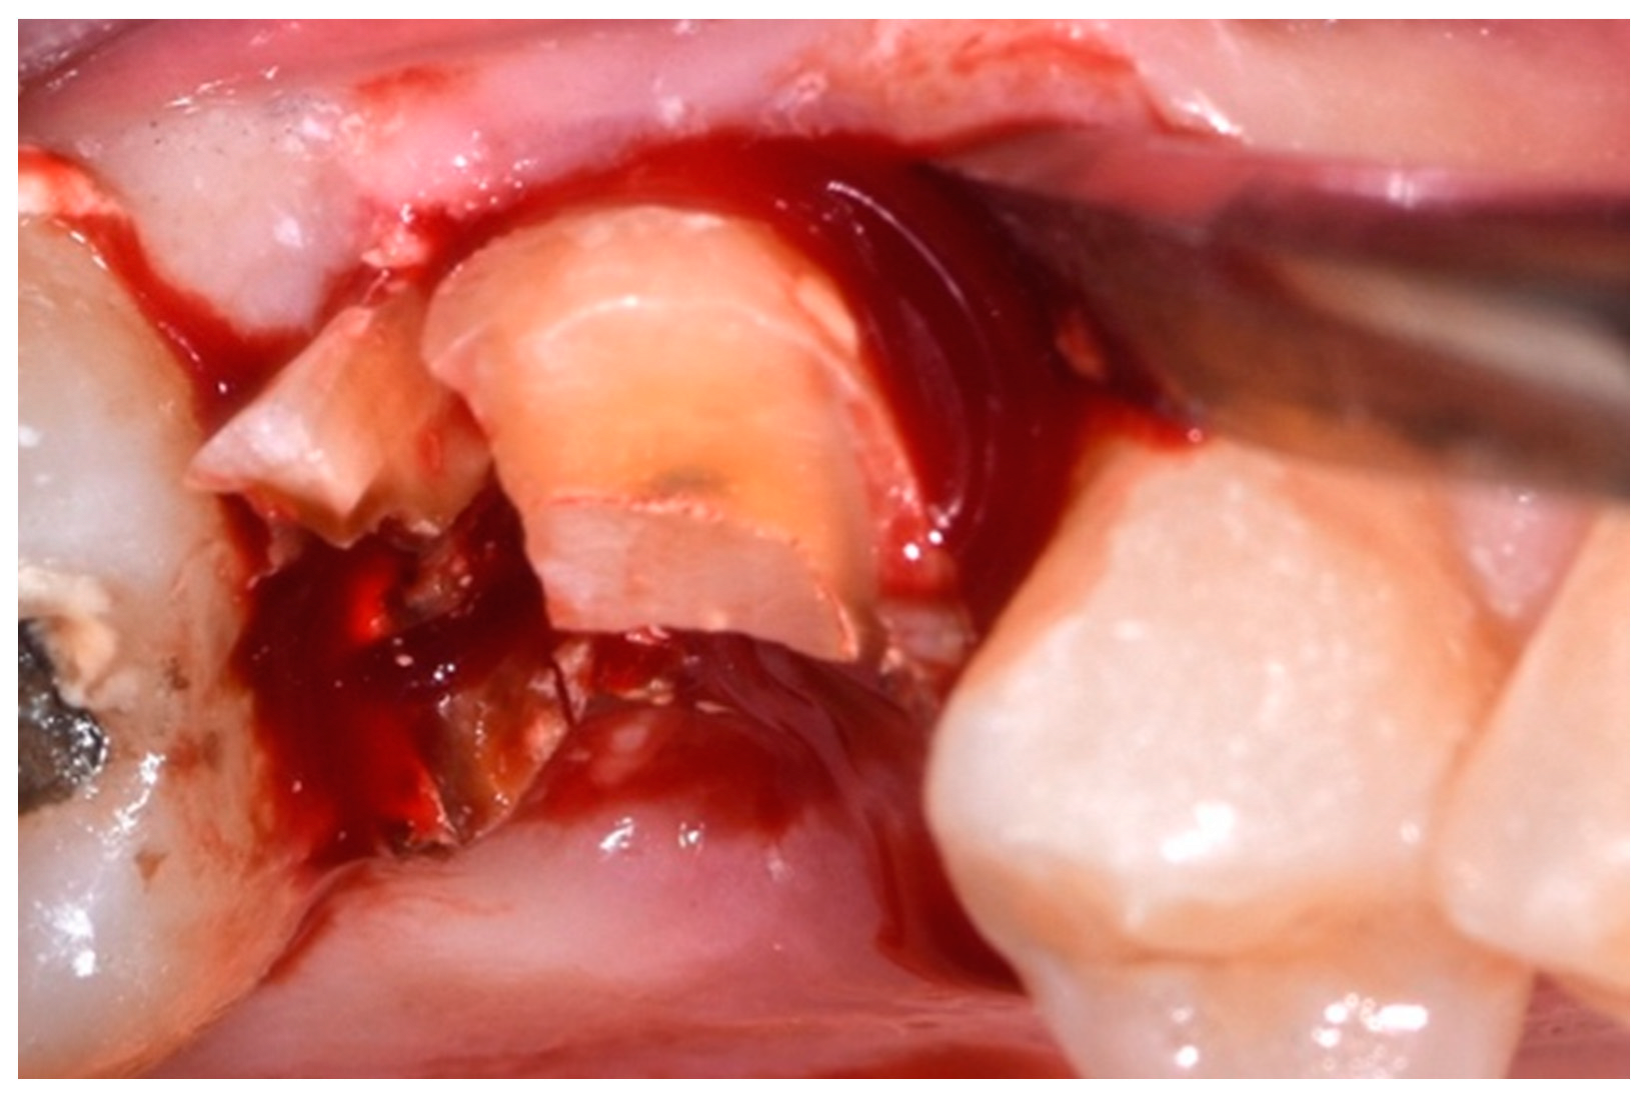

2.4. Surgical Procedure, Evaluation at Follow-Up, and Collection of Radiographic Data

- Use of inserts, pliers, and hand levers;